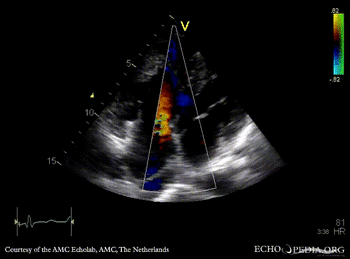

Large VSD, syndrome of Eisenmenger

AMC Echolab, AMC, The Netherlands

PSAX: Color Doppler of large VSD